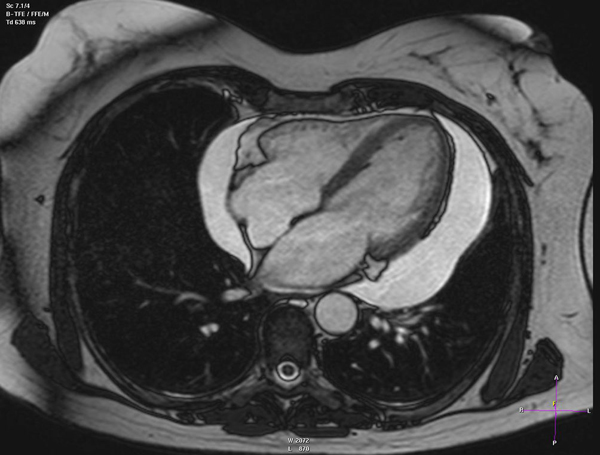

Coronary Artery Disease

Heart Failure

Valvular Heart Disease

Cardiac Inflamatory Diseases